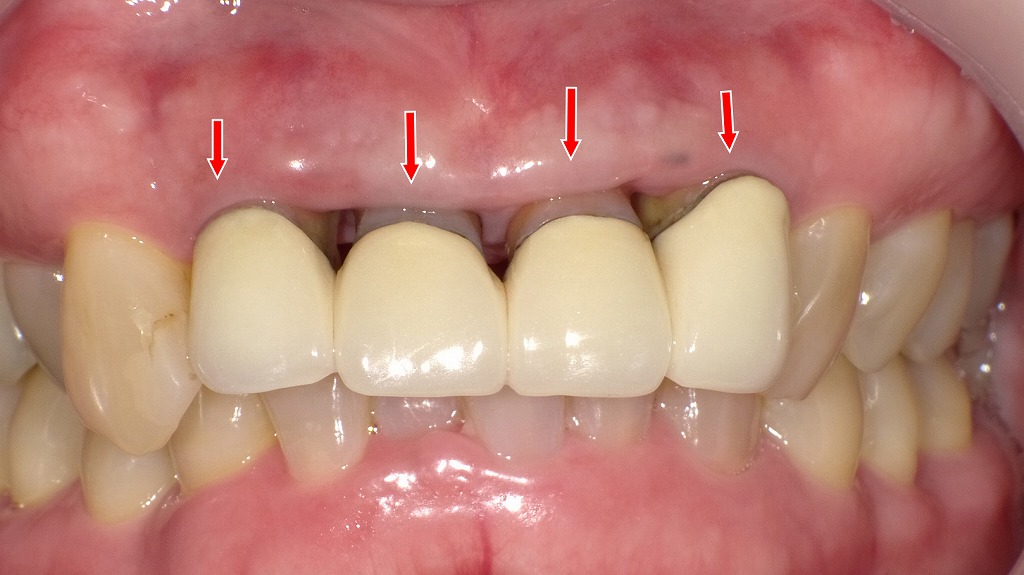

上顎2番〜2番に装着されたメタルボンドの症例。経年的な歯肉退縮により、歯ぐきが下がり、金属フレームや歯根部の黒ずみ(赤矢印)が目立っています。メタルボンドは強度に優れる一方、歯肉退縮が起こると審美性が大きく損なわれる点が欠点の一つです。

治療方針の考え方(本症例のポイント)

- 前歯部メタルボンド(2番〜2番)

- 支台歯部での歯肉退縮

- 歯肉縁下に金属色・歯根部の黒ずみが露出

- 審美障害が主訴になりやすい部位

👉 単に被せ物をやり替えるだけでは不十分で、

歯周組織(歯ぐき)へのアプローチが重要なケースです。